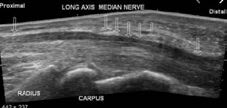

X-Ray, Ultrasound, Nerve Conduction Study

Carpal Tunnel Syndrome is a common occupational injury and can occur from lifting, typing and repetitive strain. It is caused by pressure on the median nerve.

Choosing the right Hand Therapist starts with them being able to assess your symptoms, read your X-rays or nerve conduction studies and then fabricate the right brace for you. The Physiotherapists and Occupational Therapists at Action Rehab Hand Therapy Clinic are experienced in assessing Carpal Tunnel Syndrome, reading X-rays and fabricating custom made light weight splints.

Carpal Tunnel Syndrome is a repetitive trauma and compression of the median nerve in the wrist. This can be caused by lifting, typing or repetitive bending and straightening of the fingers and thumb.